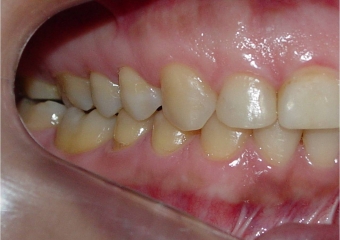

Mordida final